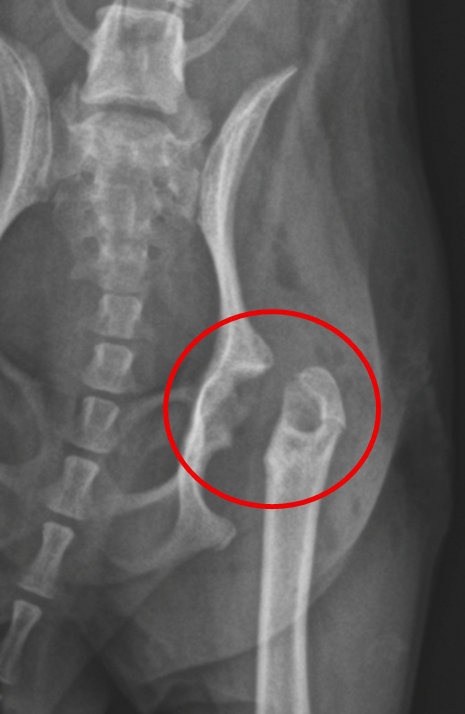

【レントゲン検査】

・同肢の骨頭にパンチアウト像および亀裂を示唆する所見がみられた (図1)

・骨折や脱臼を疑う所見は認められず